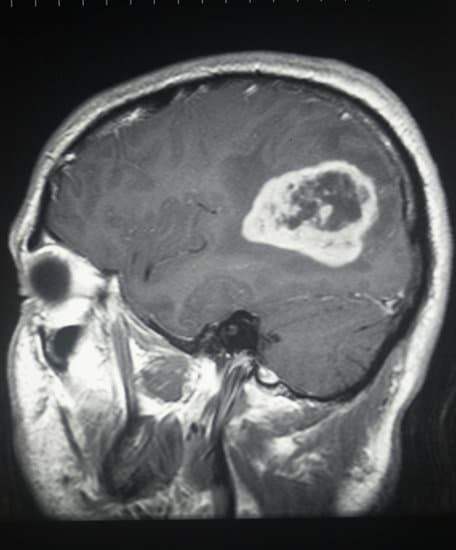

MRI (자기 공명 영상): MRI는 뇌의 상세한 이미지를 제공하며, 종양의 위치와 크기, 주변 조직으로의 영향 등을 파악하는 데 유용합니다.